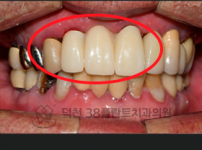

치료전후